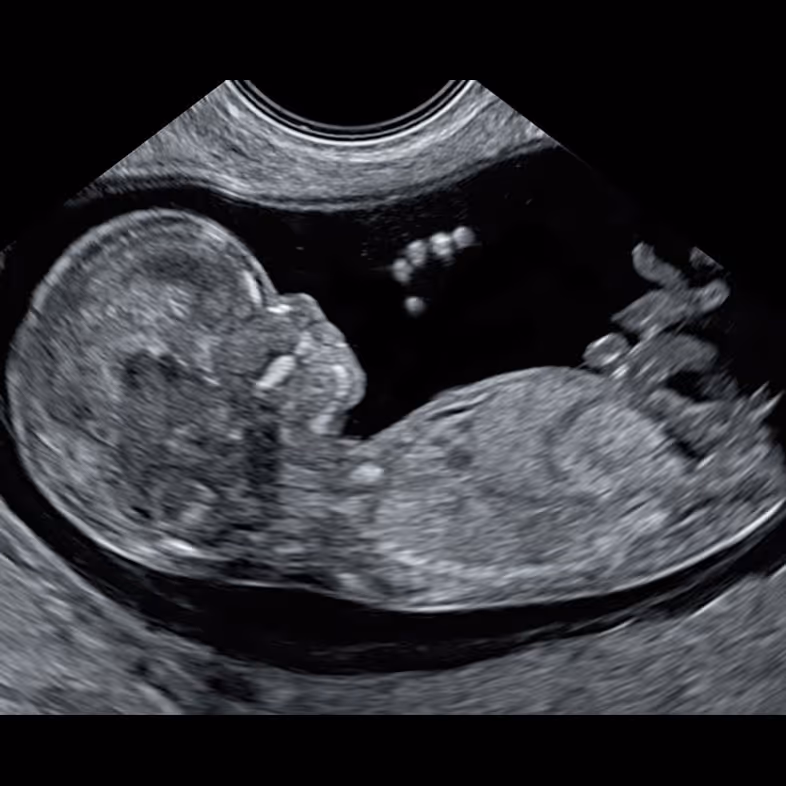

Between 10 and 12+6 weeks, the fetus roughly doubles in length and becomes about eight times larger in volume.

The NT scan is an ultrasound in early pregnancy which measures the thin pocket of fluid at the back of your baby’s neck. This measurement helps estimate the chance of some chromosomal conditions (like Down syndrome) and certain structural problems, especially heart defects.

You lie on the couch and gel is placed on your tummy. The sonographer moves the probe over your abdomen to see the baby on the screen, checks the heartbeat and general development, and then measures the NT at the back of the neck.

The NT scan is usually done once between 11 and 14 weeks of pregnancy, when your baby measures about 45–84 mm from head to bottom (crown–rump length). After this window the measurement is not reliable.